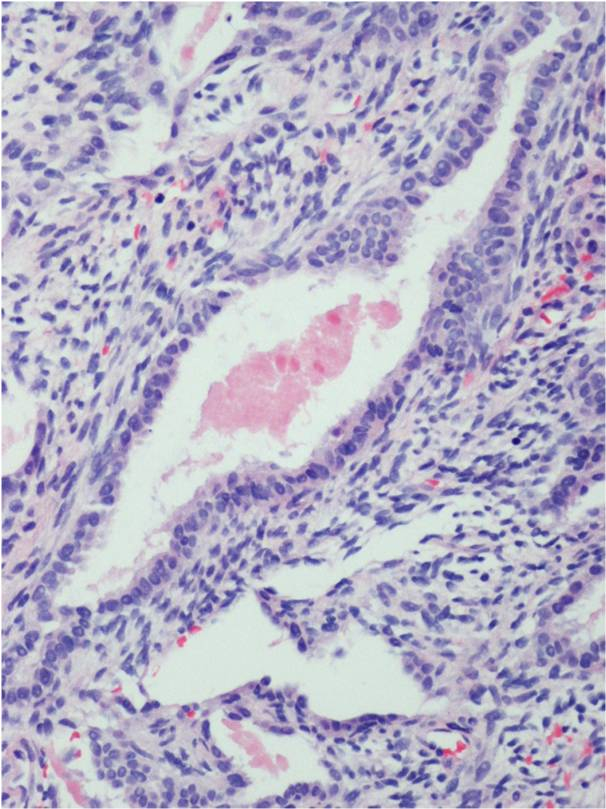

Synovial Sarcoma is composed of two different cell types

Spindle cell (small, uniform, and ovoid cells with pale nuclei and the cytoplasm is sparse)

Epitheloid cell (ovoid nuclei and abundant cytoplasm)

Biphasic form is composed of both epithelial-cell and spindle-cell components in equal proportions (Fig. 6-8)

Monophasic Epithelial type is difficult to differentiate from adenocarcinoma without cytogenetics and immunohistochemistry.